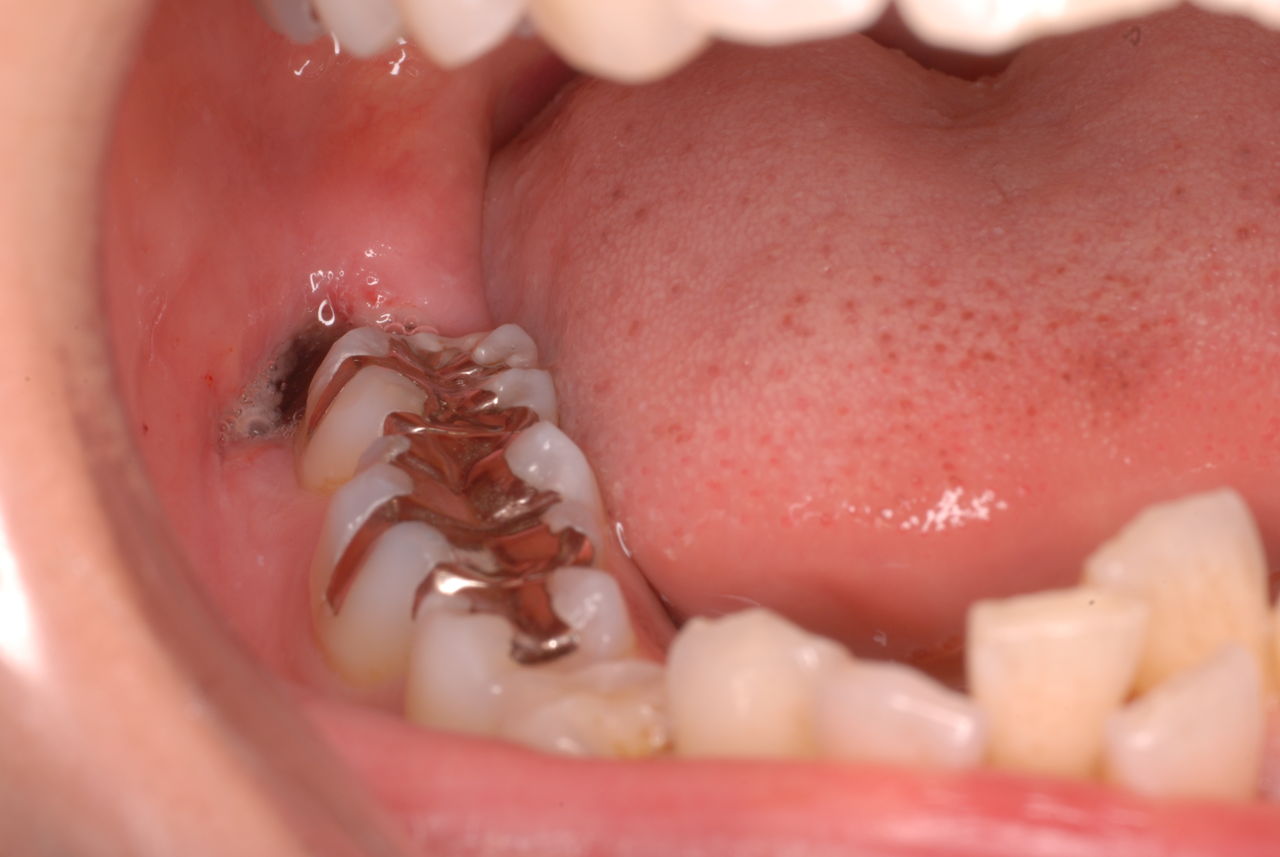

クラスプという歯を取り囲むワイヤ−が折れたりしてまともに機能していません。構造的な問題もあるのでしょうがヒビも目立ちます。殆ど使わずに御蔵入りとなったようです。値段の問題からかそうではないか判然としませんが、入れ歯というのは残りの歯や歯周病の治療がある程度完了してからでないと良い機能的な入れ歯などはできません。せいぜい治療中用の簡素な物を作成して歯や歯茎の病気が治るのを待ちながら様子をみるしかないのです。